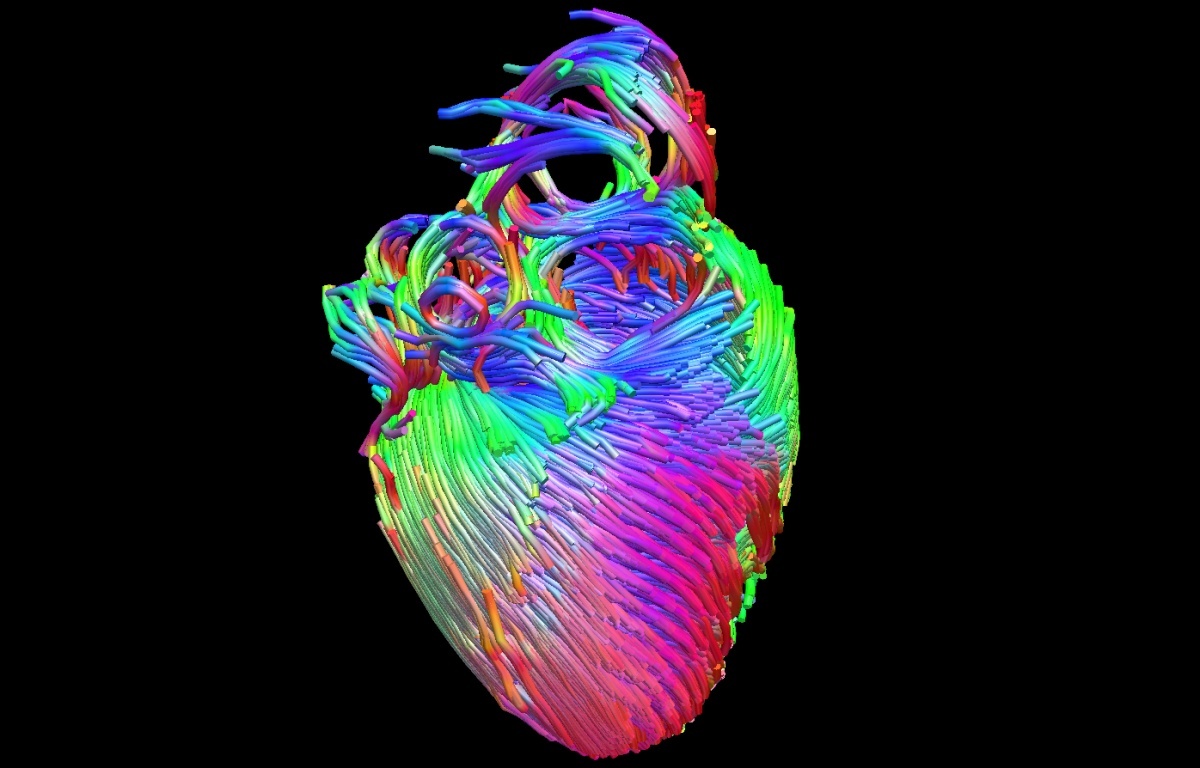

Diffusion Tensor Imaging (DTI) - Fiber Tracking - Imagilys

Diffusion Tensor Imaging (DTI) - Fiber Tracking - Imagilys

Diffusion Tensor Imaging (DTI) - Fiber Tracking - Imagilys

Using Diffusion Tensor Imaging (DTI), axonal fiber tractography

Diffusion tensor imaging and fiber tractography | Radiology